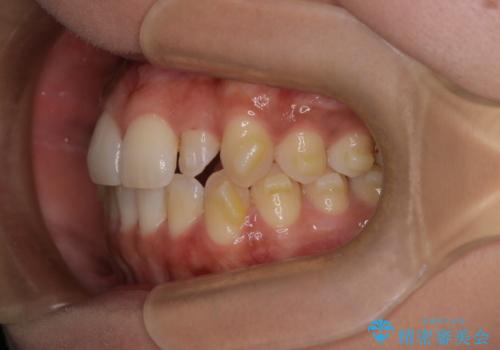

反対咬合と前歯のガタガタを非抜歯で改善

- 患者様は、上下の前歯のガタガタと反対咬合(下の歯が上の歯より前に出ている状態)を主訴として来院されました。診断の結果、抜歯を行わずに治療を進めるため、臼歯を遠心移動させてスペースを作り、IPR(インタープロキシマルリダクション)で歯間を調整する治療計画を立てました。インビザラインを使用して、透明で目立たない矯正装置により、歯列を整えながら噛み合わせも改善することを目標としました。

非抜歯での治療では、限られたスペースの中で効率的に歯を動かす必要があります。本症例では、臼歯を後方に移動させる遠心移動を行い、歯列のガタガタを改善しました。また、IPRを適切に行うことでスペースを確保し、歯根や歯肉への負担を最小限に抑えながら治療を進めました。インビザラインを使用することで、治療中も目立ちにくく、患者様の日常生活への影響を軽減しました。結果として、抜歯を行わずに美しい歯並びと自然な噛み合わせを実現し、患者様には大変満足していただけました。